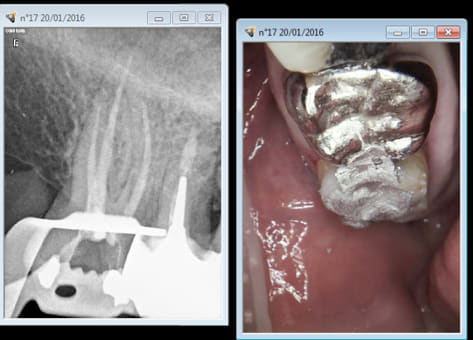

C'est pas fini vos conneries ? J'ai voulu poser un bridge aujourd'hui de 45 à 47 et la 17 est descendue de 2 mm en une semaine ( pas la 16 va comprendre) du coup endo de 17 et lifting occlusal. -))))

L'exception qui confirme la regle. -)

En plus hard à anesthésier meme au QS re exception qui confirme la regle. -)))

40 mn après, Tout est rentré dans l'ordre promis je ferais une provisoire sur 17 -)